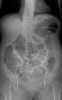

Trauma with colonic perforation

Gastrointestinal perforation, also known as ruptured bowel, is a hole in the wall of part of the gastrointestinal tract. The gastrointestinal tract includes the esophagus, stomach, small intestine, and large intestine. [Source: Wikipedia ]